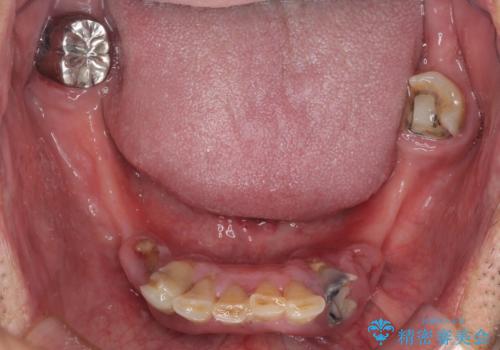

- どこで咬んでよいのか分からないとのことで来院された患者様です。

歯冠の崩壊した奥歯と、前歯の一部でした咬み合うことができず、入れ歯も試したものの、装着することができなかったようです。

全顎的にインプラント補綴を行うことも検討しましたが、費用面から、インプラントを土台とした入れ歯(インプラント・オーバーデンチャー)による補綴治療を行うこととしました。